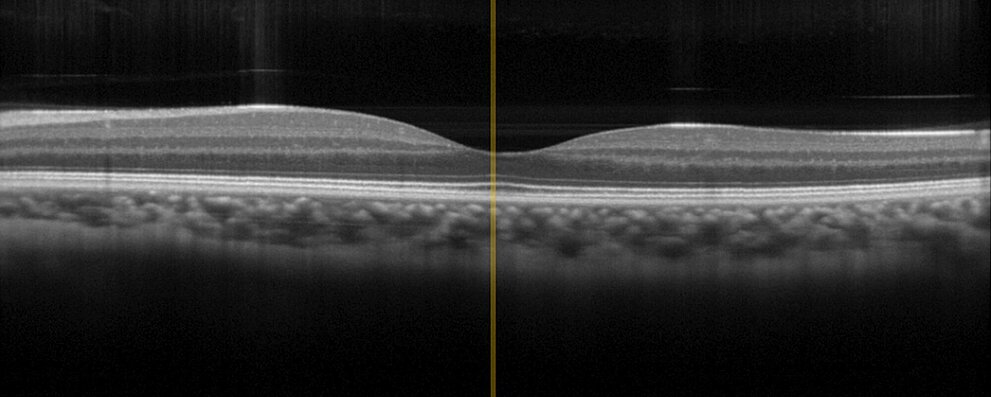

Endoskopie und In-vivo-Diagnostik gehören zu den anspruchsvollsten medizinischen Technologien, da sie im bzw. am lebenden Organismus eingesetzt werden. Höchste Zuverlässigkeit ist hier unabdingbar. Die jahrzehntelange Erfahrung von PI als Zulieferer für Unternehmen der Medizintechnik und die 30-jährige Erfahrung als Hersteller von Piezokomponenten, sind wesentliche Assets, die PI in die Entwicklung und Herstellung von Baugruppen und Subsystemen einbringt. So bietet PI beispielsweise gleich mehrere Antriebe für die variable Fokussierung von Chip-on-the-Tip Endoskopen. Und für die optische Kohärenztomographie (OCT) mit Anwendungen in der Ophthalmologie oder Dermatologie, bietet PI für eine präzise Positionierung der Optik verschieden Antriebstechnologien, die auf gerätespezifische Anforderungen wie Baugröße oder Stellweg angepasst werden können.